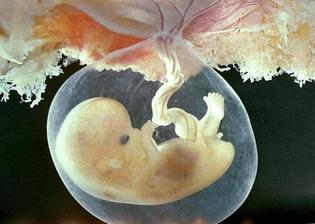

15.5. první KO u dr. potvrzeno těhotenství 6tt (gestační a žloutkový váček)

29.4. druhá KO u dr 7+3, 12,3mm a srdíčko bije